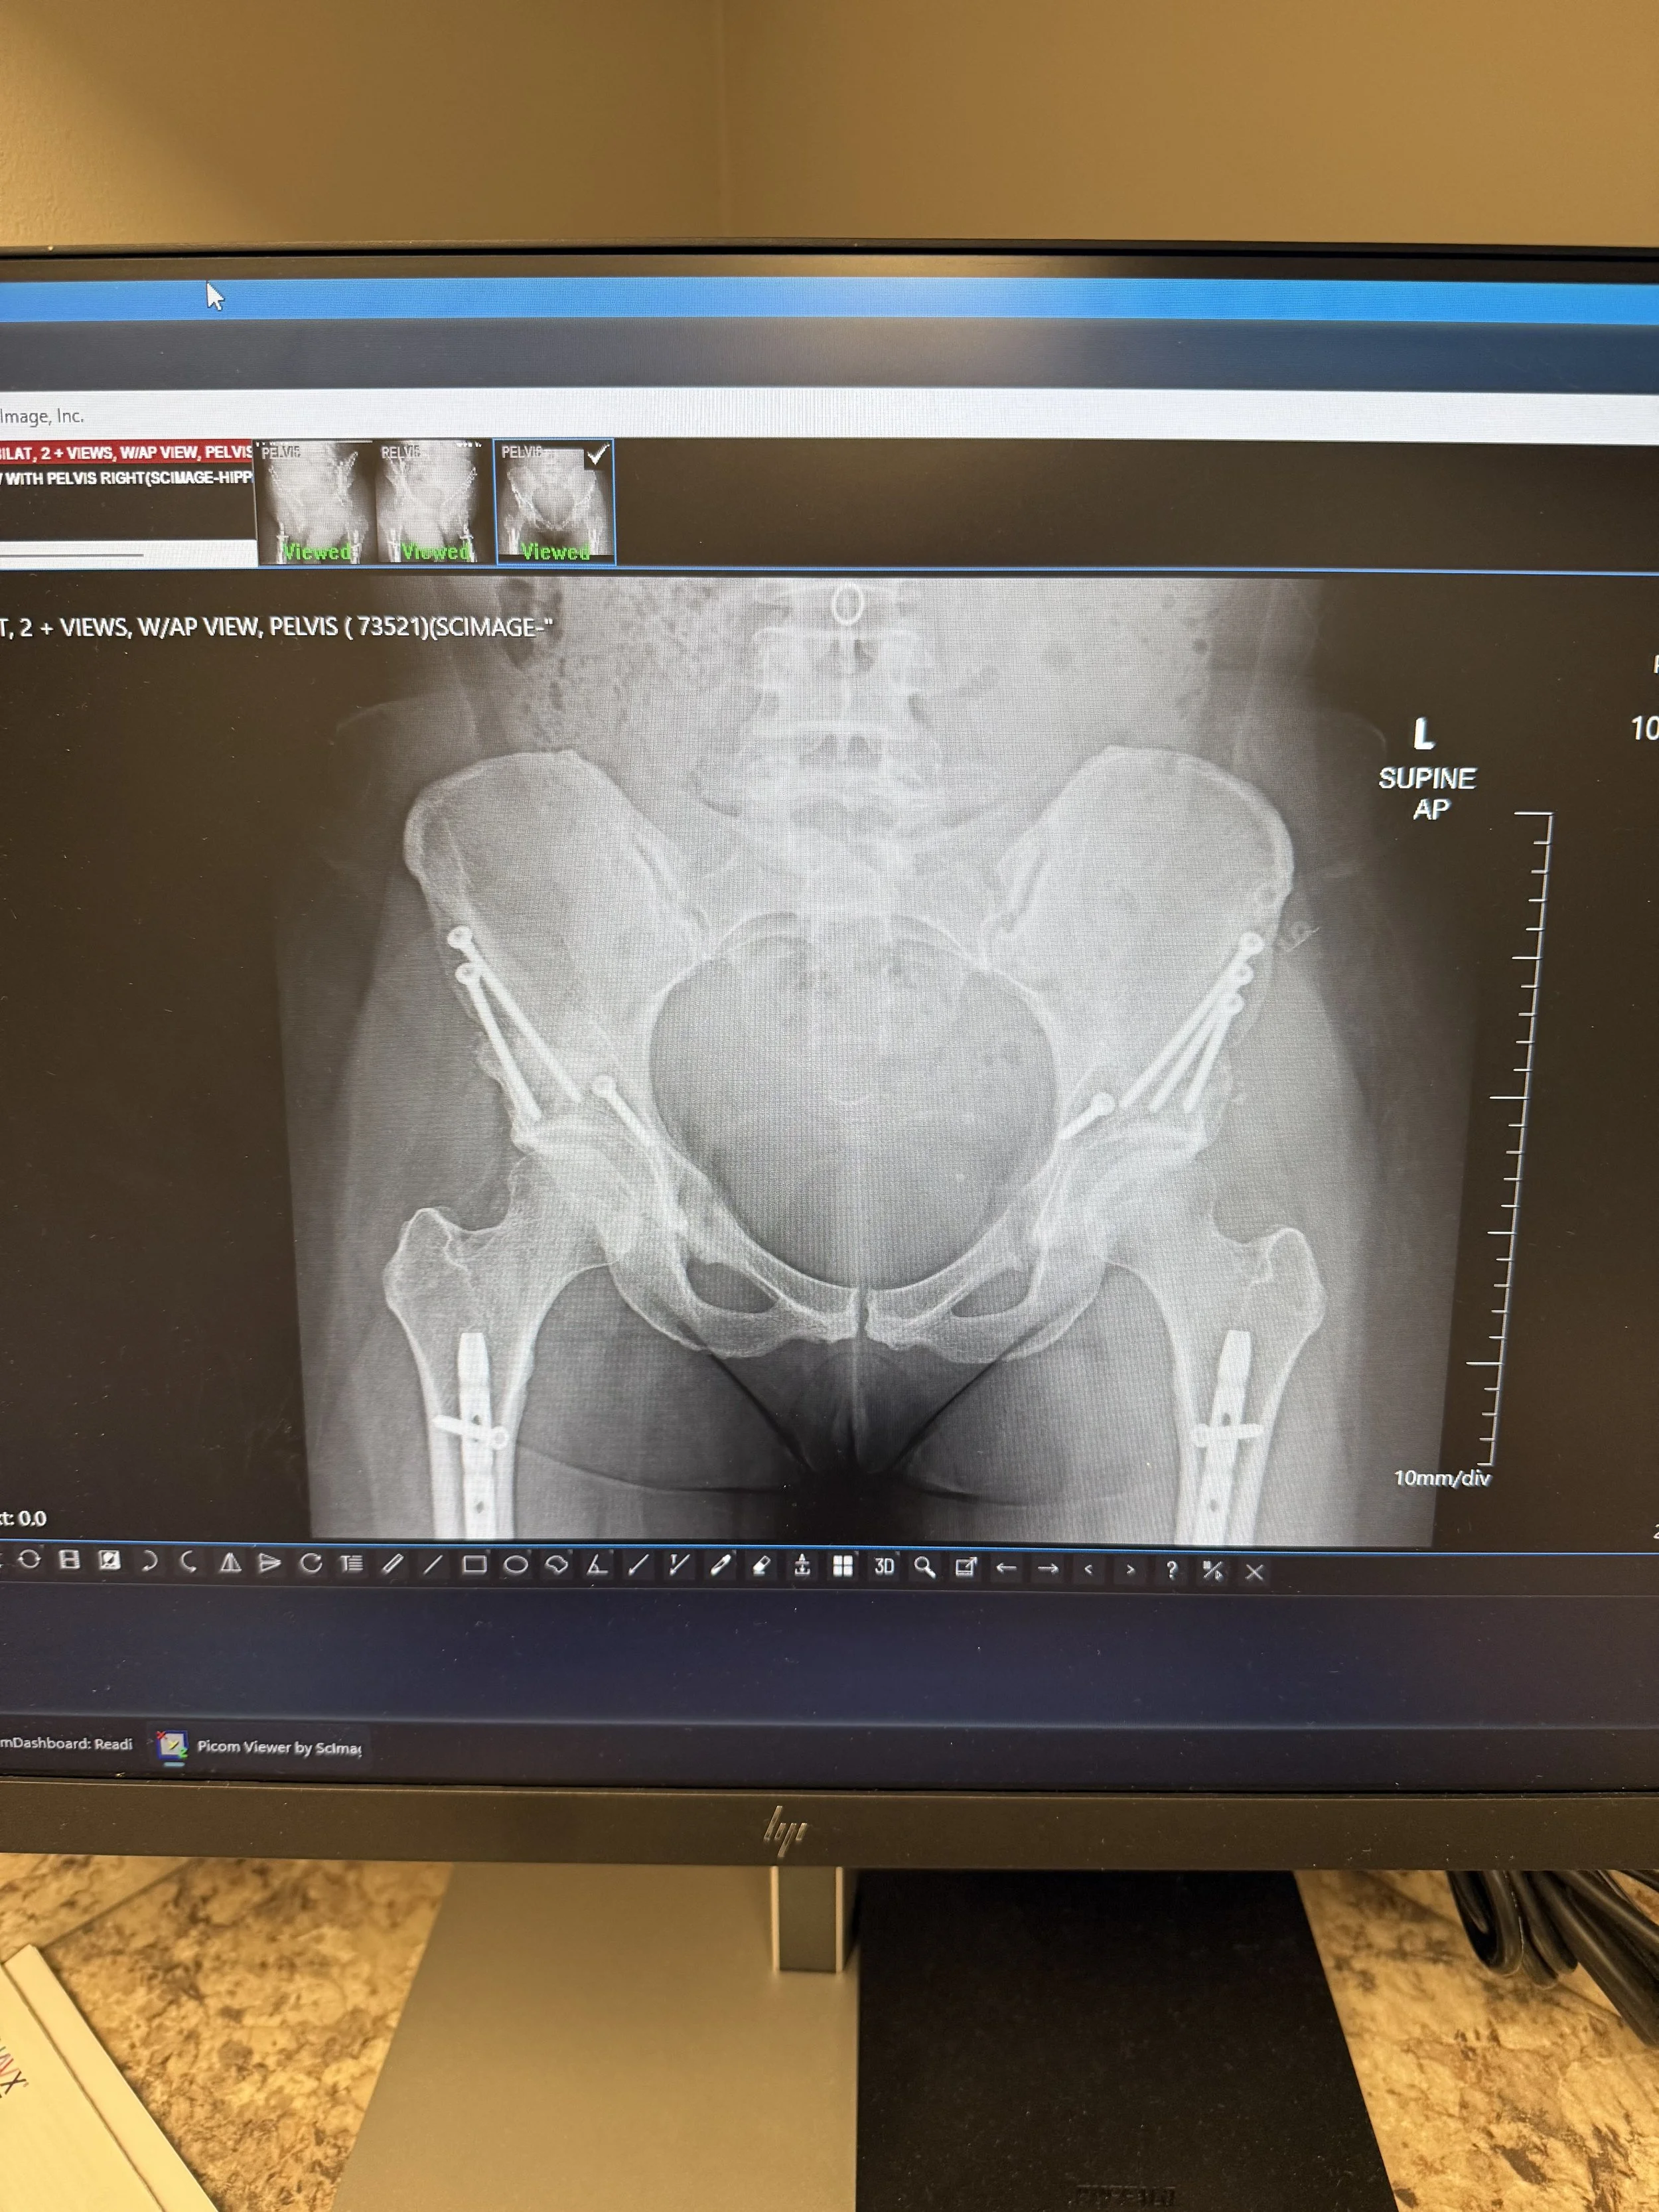

At my eight-week PAO post-op, x-rays of both hips showed positive healing progress. When I brought up my pelvic pain, the PA seemed baffled at how it could be related to the PAO. At his suggestion, I called my arthroscopy surgeon’s office in Boulder to let them know I was in town and dealing with new symptoms. They got me in that afternoon — which was both impressive and overwhelming. It was a really big day.

What I learned: pelvic pain could stem from multiple sources — pudendal nerve involvement, pelvic floor tension, adductors over-tightening, lumbar overworking. We took lumbar x-rays and discovered bilateral pars defects at L5 — structural weaknesses in the vertebra that allow it to slip slightly forward over S1 and potentially cause nerve entrapment, among other things. More information. More layers. More to unpack.

I said it last post and I’ll say it again: so many things could be affecting me! Some of this is visible — healing hips on x-ray. Some of it isn’t — nerve pain, lumbar instability, the cumulative toll of surgeries last August and the accident three and a half years ago. All of it is layered together.

Some things show up clearly on imaging. Others live in the spaces in between. What’s visible isn’t always what hurts the most.